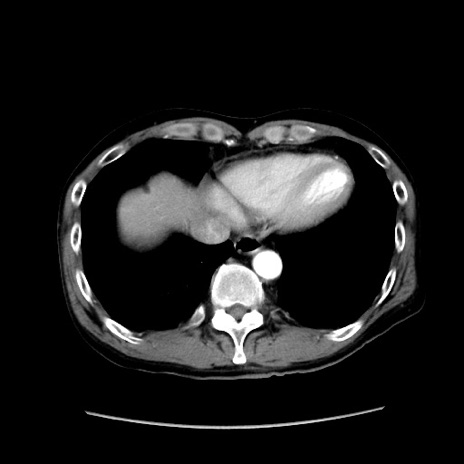

症例37(横断像)

【症例】40歳代 男性

【主訴】腹痛

【現病歴】4時間ほど前に電車に乗車中に臍部上より腹痛出現。徐々に増悪し起立困難となり、救急外来受診。生ものは数日食べていない。今朝お雑煮を食べた。

【身体所見】BT 36.8℃、BP 117/84mmHg、HR 91/min、SpO2 97%、苦悶様、腹部:臍上部広範囲圧痛あり、反跳痛±

【データ】WBC 8100、CRP 0.03